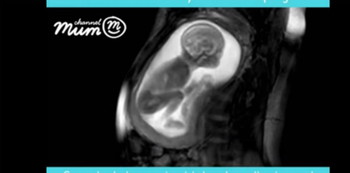

Melihat bagian-bagian tubuh janin secara rinci dengan dengan teknik ultrasound memang bukan hal yang mudah. Namun iFind Project menggunakan teknologi MRI, yang memanfaatkan gelombang medan radio magnet yang kuat dan aman untuk kehamilan. Itulah yang membuat penampakan janin jadi lebih jelas.

Tim iFind Project yang berbasis di London terdiri dari para peneliti dan dokter gabungan yang selama ini ahli di bidang teknik USG, MRI dan komputasi untuk menciptakan gambar janin berusia 20 minggu yang paling rinci.

Mereka bahkan membuat video berdurasi 24 detik yang berasal dari salah satu percobaan mereka dan memberikannya kepada laman Channel Mum untuk berbagi dengan ibu hamil di seluruh dunia.

Di dalam video ini terlihat adanya janin berusia 20 minggu dari seorang ibu yang tidak disebutkan namanya. Dalam video ini, bahkan Anda bisa melihat tali pusar, putaran kepala, dan bahkan kaki bayi yang sedang menendang ibunya.